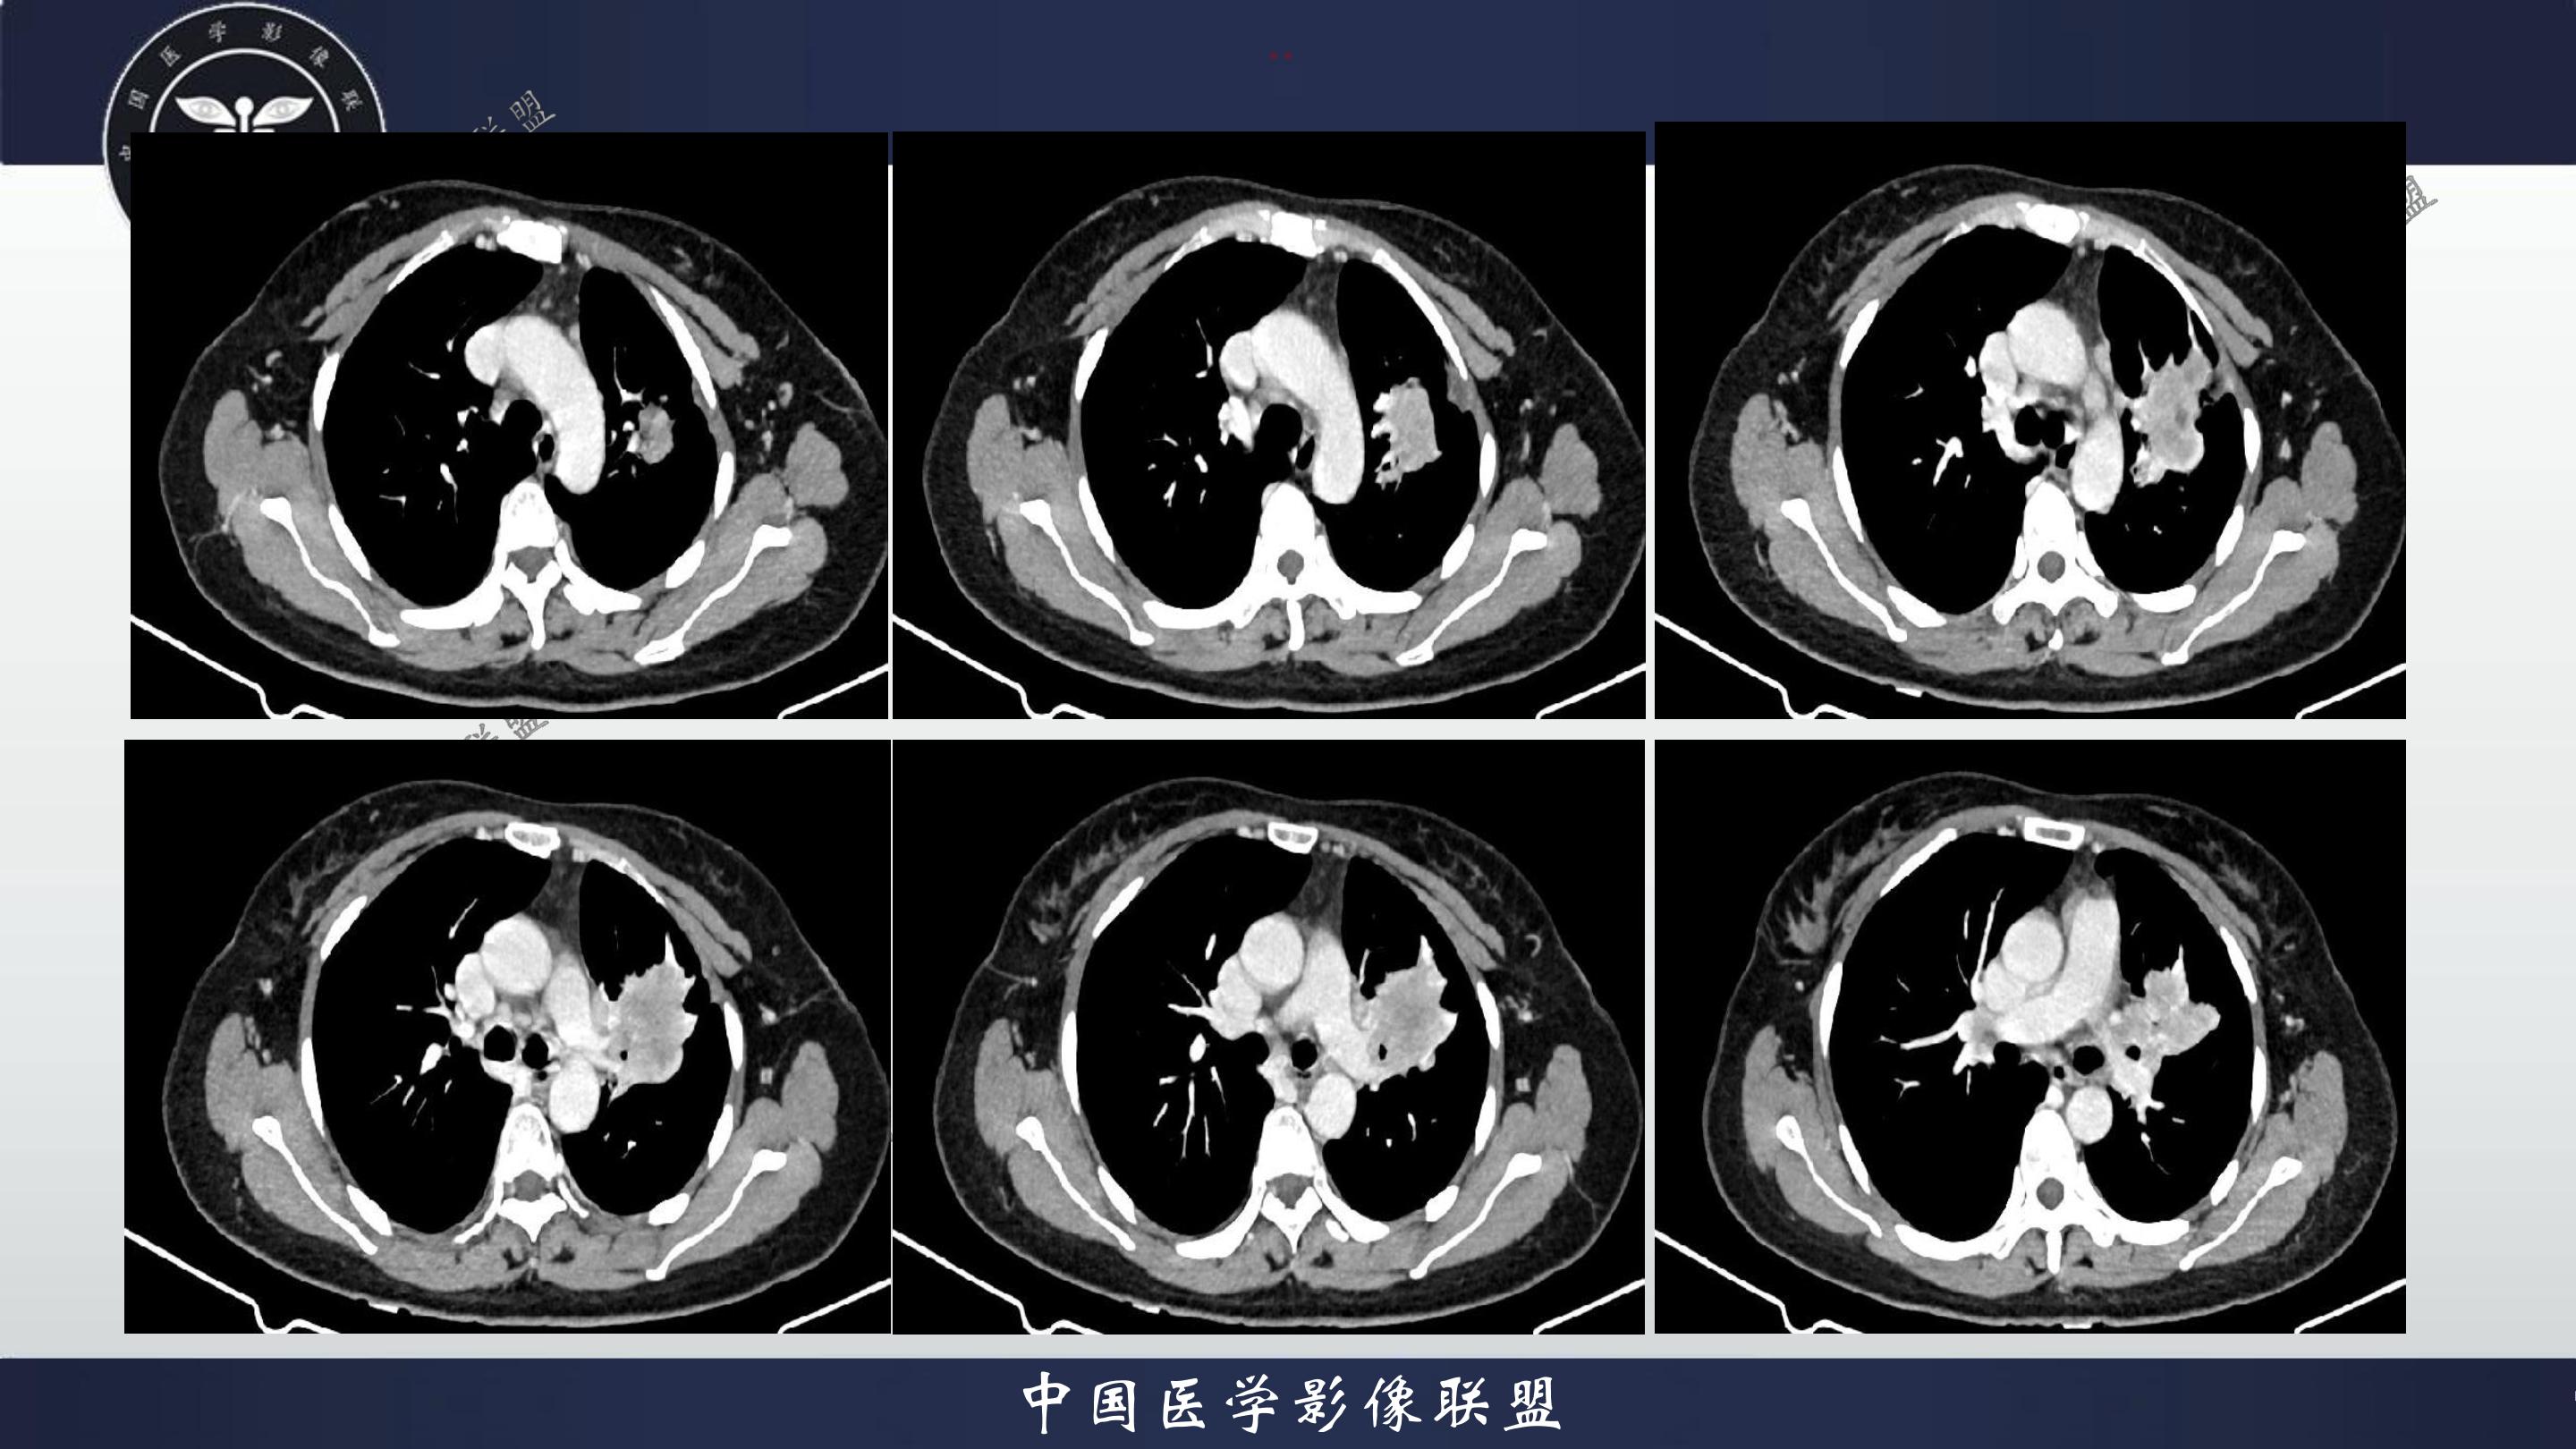

老年女性,咳嗽、咳痰伴痰中带血3月

3月前患者无明显诱因出现咳嗽、咳痰,呈阵发性咳嗽,咳大量黄色脓痰,痰不易咳出,伴痰中带血,量少,具体量不详,伴鼻塞、口干、乏力,活动后感喘息、劳累,休息后缓解,无发热、畏寒,无盗汗,无心慌、胸闷,无腹痛、恶心、呕吐,无头昏、心前区压榨性不适,院外予以输液及口服药物治疗后症状无明显缓解,现为系统诊治就诊我院门诊,门诊以“社区获得性肺炎”收入我科。病来精神、饮食、睡眠尚可,大小便正常,体重无明显变化。

既往有高血压病史10+年,血压最高160/70mmhg,自诉长期口服降压药物治疗,具体药物名称不详;8+年前患者有胆囊结石病史,自诉当时予以手术治疗后好转出院,具体不详;否认“糖尿病、冠心病"等疾病史。否认“肝炎、伤寒、结核”等传染病史;否认已知药物及食物过敏史,否认烟酒史

查体:T:36.8℃P:82次/分,R:20次/分,BP:135/82mmHg,spo2:96%.神清合作,咽稍充血,双侧扁桃体无肿大;双肺呼吸音粗,双肺可闻及少许湿性啰音,未闻及哮鸣音;心界不大,心率82次/分,律齐,心音低钝,各瓣膜听诊区未闻及杂音,腹软,中上腹压痛,无反跳痛及肌卫,肝脾未扪及。双下肢无水肿。

4.辅查:生化报告(2024-11-14 13:06:51)尿素氮或尿素:10.1mmol/L↑,尿酸:342umol/L↑,钾离子:3.16mmol/l↓,尿常规报告(2024-11-14 13:11:41)隐血:+2,凝血报告(2024-11-14 13:16:37)血浆D-二聚体测定:0.62ng/mL↑,生化报告单(2024-11-14 16:14:45)MP滴度(1:40):弱阳性,PCR报告(2024-11-14 16:50:37)人鼻病毒核酸(HRV-RNA)定性:阳性,传染性指标、粪便常规、BNP、心肌特异蛋白、CEA、肝功能、血脂、红细胞沉降率未见明显异常。血气分析回示:PH 7.443 PCO2 28.3mmhg PO2 90.9mmhg HCO3- 19.53mmol/L 氧和指数432.9mmhg;心电图回示:1.窦性心律2.T波改变(Ⅲ倒置、aVF低平)